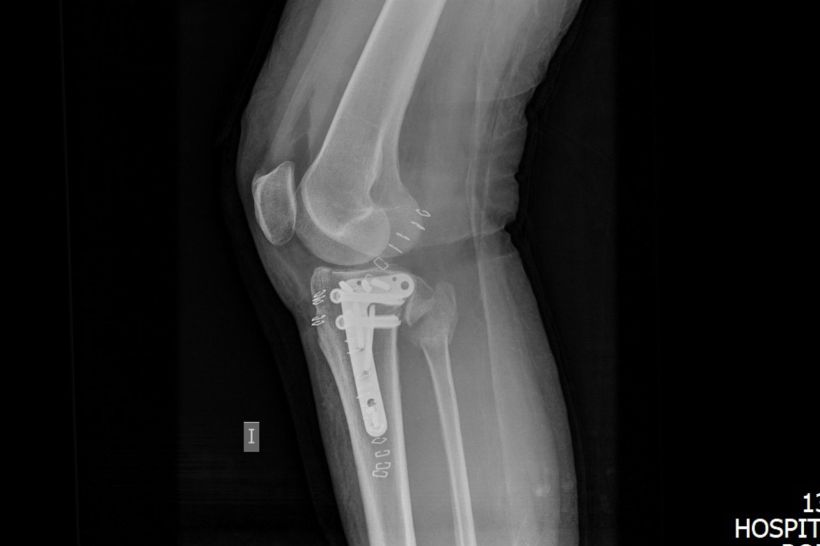

The ambulance eventually showed up and loaded her into the back, I rode shotgun and asked where we were going. Porto Cristo, I was told. The same Porto Cristo where we’d both said we wouldn’t mind spending a couple of nights so I feel like some manner of malignant genie is cackling manically somewhere because Tarrant at the very least would be spending a few nights there. I think the enormity of what she’d done finally hit me when, after the x-rays, they said she needed surgery which would happen the following day as long as the insurance agreed to cover it. We weren’t going home on Sunday now, that much was apparent. Again, the insurance were great. I chased them up a couple of times because the hospital, which was private, were anxious to get guarantee of payment before slicing her open, then someone from Axa called me the following day and asked if she was wearing a helmet. Well yes, yes she was. We all were, I could even prove it if necessary because Laura was taking photos. Proof wasn’t asked for though, guarantee of payment was sent and Tarrant was scheduled to have chunks of mental permanently embedded into her fractured bone.

Surgery went well thank fuck, but she’s not allowed to put any weight on it for six weeks which is fair enough. She’d fractured her tibial plateau in several places and bits of bone were floating about in there hence the surgery, and she’d got a clean break on her fibula. Ah, falling over in your forties. Gone are the days of just your pride being a little bit bruised which is easily remedied with a Jägerbomb and the insistence that you styled it out. You’re talking morphine and hospital food, which was actually fucking appalling considering it was a private hospital. Vegetables boiled to within an inch of their lives, greasy but somehow tasteless soups, unidentified reconstituted meat stuffs, little bread rolls that were so fucking stale you could build houses with them. I started taking her a serrano baguette, an ensaïmada (which is an insanely delicious, fluffy pastry liberally sprinkled with so much icing sugar you end up looking like you’ve faceplanted a pile of cocaine) and a coffee from a lovely little bakery in Porto Cristo that tolerated my awful Spanish with a smile.